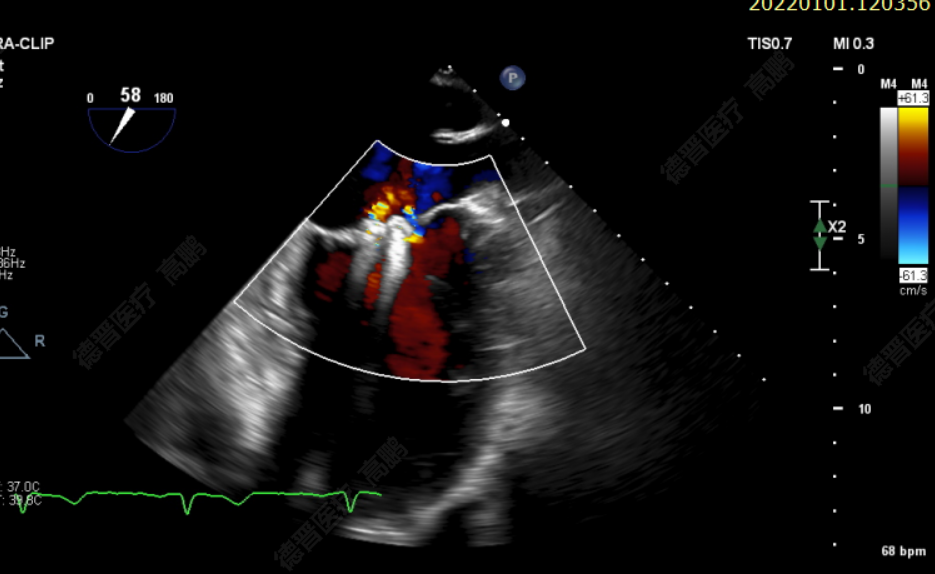

患者为75岁老年男性。反复气促、胸闷2年余,加重1月就诊福建省立医院。经胸心脏彩超提示:二尖瓣后叶重度脱垂伴返流4+、后叶腱索断裂;经食道超声心动图提示:二尖瓣后叶P2区重度脱垂伴返流4+。既往有高血压病、冠心病病史。